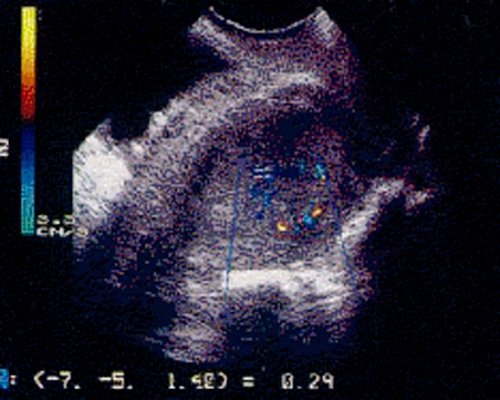

Интенсивный внутриопухолевый кровоток выявлен у 78,3% больных. При цветовой допплерографии зарегистрированы рассыпной тип кровоснабжения матки, по ходу сосудистого пучка, богатая васкуляризация миометрия со средними и низкими показателями резистентности сосудов, а также неоваскуляризация эндометрия с "мозаичной" формой картирования и низким уровнем периферического сопротивления новообразованных сосудов. Из них в 21,7% наблюдений отмечен преимущественно ве нозный тип внутриопухолевого кровотока в бассейне неоваскуляризации и с максимальной скоростью венозного кровотока - 8,3 см/с (колебания 4-13 см/с).

Интенсивность кровотока зависела от формы роста опухоли: при экзофитной форме отмечен интраопухолевый тип неоваскуляризации, при эндофитной - интенсивный интра- и периопухолевый тип кровотока, богатая васкуляризация миометрия (рис. 1).

а) Интра- и периопухолевый.

б) Интраопухолевый.